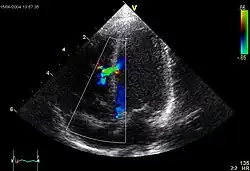

There are various ways of diagnosing this congenital heart defect both prenatally and postnatally, these methods include:[44][45]

- Ultrasound

- Echocardiogram